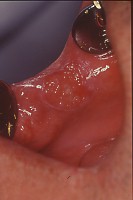

症例 症例1:口角部に近い頬粘膜に癌があります。